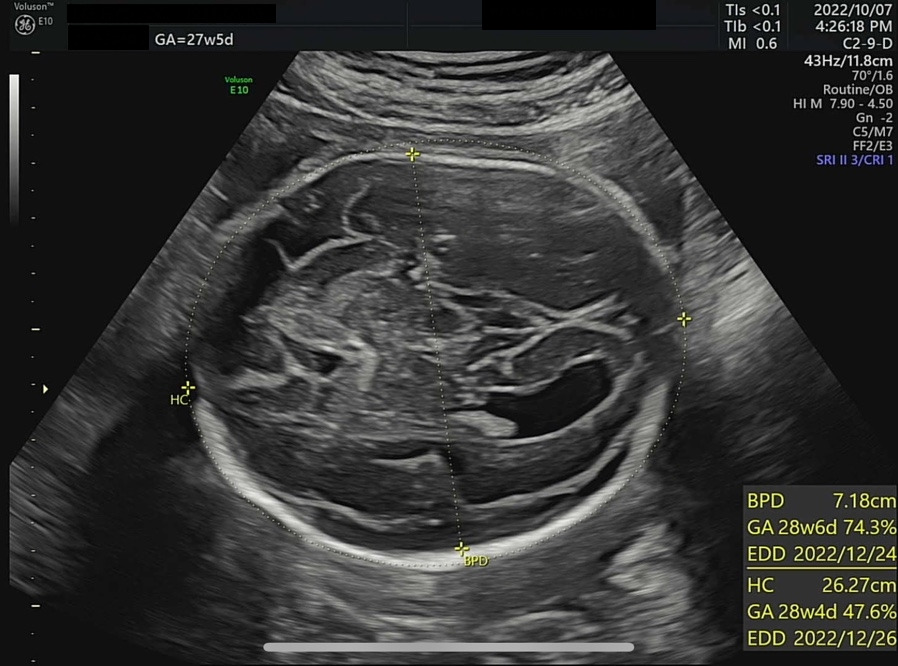

오늘은 병원에서 4D 입체 초음파를 찍기로 예약한 날이다. 입체 초음파는 아기의 모습을 입체적으로 사진 찍듯이 볼 수 있는데, 27주쯤에 찍어야 아기도 통통하게 살이 올라 예쁘게 찍힌다고 하여 이때 예약했다. 초음파실에 들어가서 아기가 주수에 맞게 잘 컸는지부터 확인했다. 2주 전 860g 정도였던 써니는 벌써 1kg를 돌파하여 1096g이 되었다. 임신 28주 이후에 체중이 1000g을 넘은 아기는 조산하여도 NICU(Neonatal Intensive Care Unit, 신생아 집중치료실)에서 치료를 받을 경우 생존 가능성이 95% 이상이다. 가장 친한 친구 중 한 명이 NICU 간호사인데, 매번 써니의 체중을 물어보았었다(직업병..?). 이제 1kg를 넘었으니 혹시나 세상에 일찍 나와도 이모한테 가면 살 수 있다. 그래도 이모 일터에는 가지 말자 써니야...

왼쪽부터 심박수, 양수량 확인, 머리 좌우 직경과 둘레 그리고 그에 따른 예상 분만일. ± 1주정도는 일반적이다.